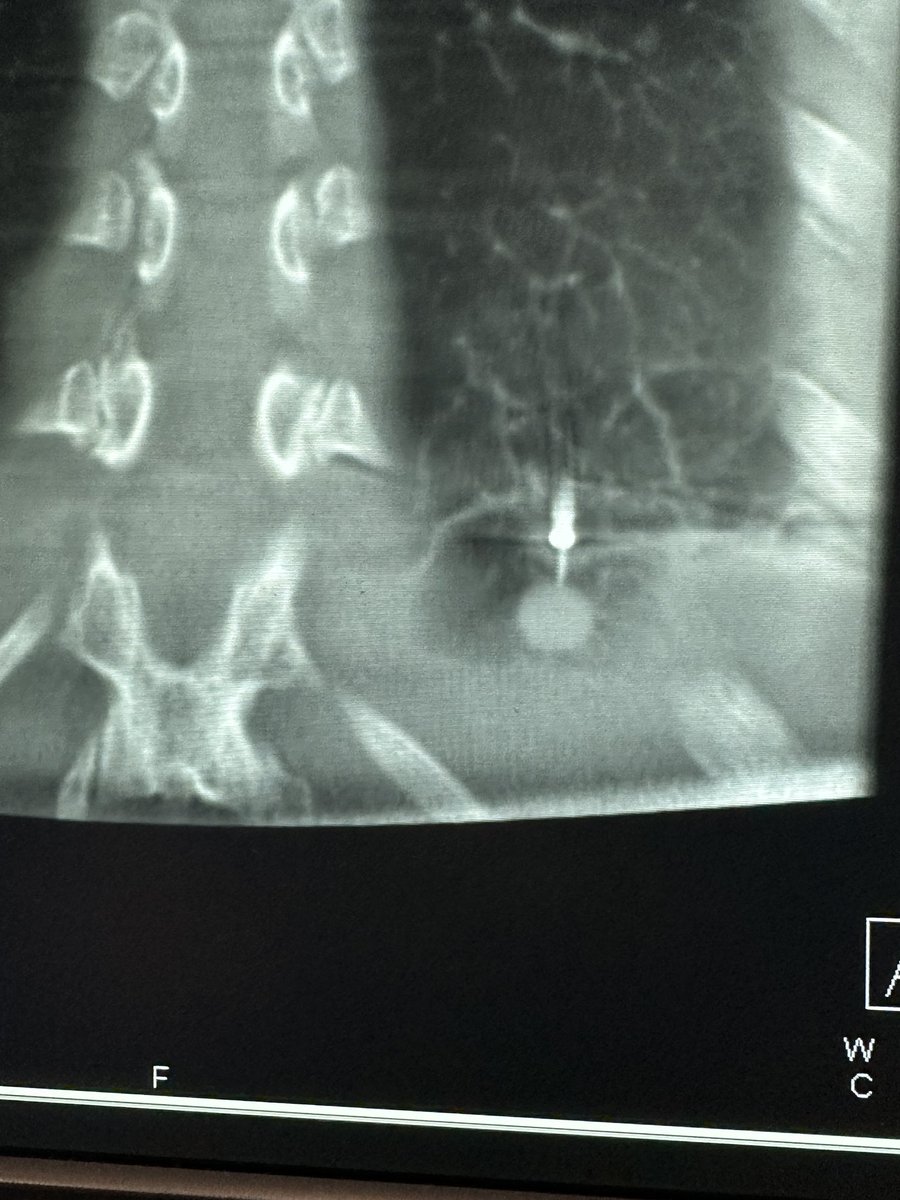

Bhadra & Condra CBCT Bronchoscopy

If you don't like the road you are on, pave a new one: Cone Beam CT Bronchoscopy.